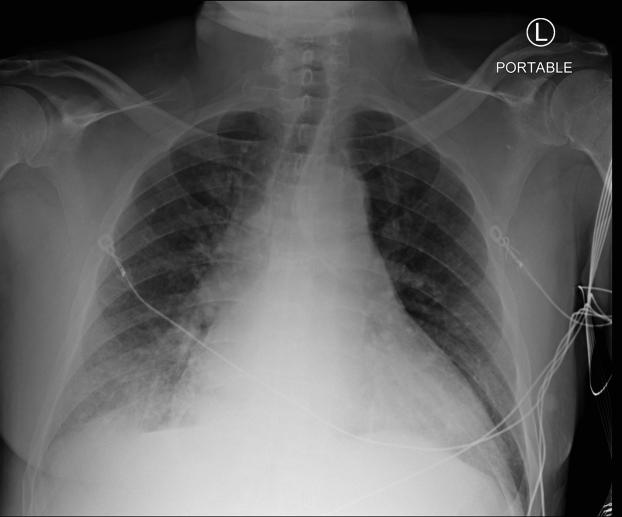

Cardiac beriberi, or heart failure due to thiamine deficiency, is considered rare in the developed world. The diagnosis is often only considered in limited populations such as those with chronic alcoholism. Alternatively, the disease can be mislabeled as "alcoholic cardiomyopathy" or "nonischemic cardiomyopathy." The following 2 cases illustrate the need to expand our vigilance to other at-risk populations.

心脏型脚气病,即因硫胺素缺乏引起的心力衰竭,在发达国家被认为较为罕见。通常只有在特定人群中才会考虑该诊断,比如慢性酒精中毒患者。另外,这种疾病可能会被误诊为“酒精性心肌病”或“非缺血性心肌病”。以下两个病例表明,我们需要提高对其他高危人群的警惕。